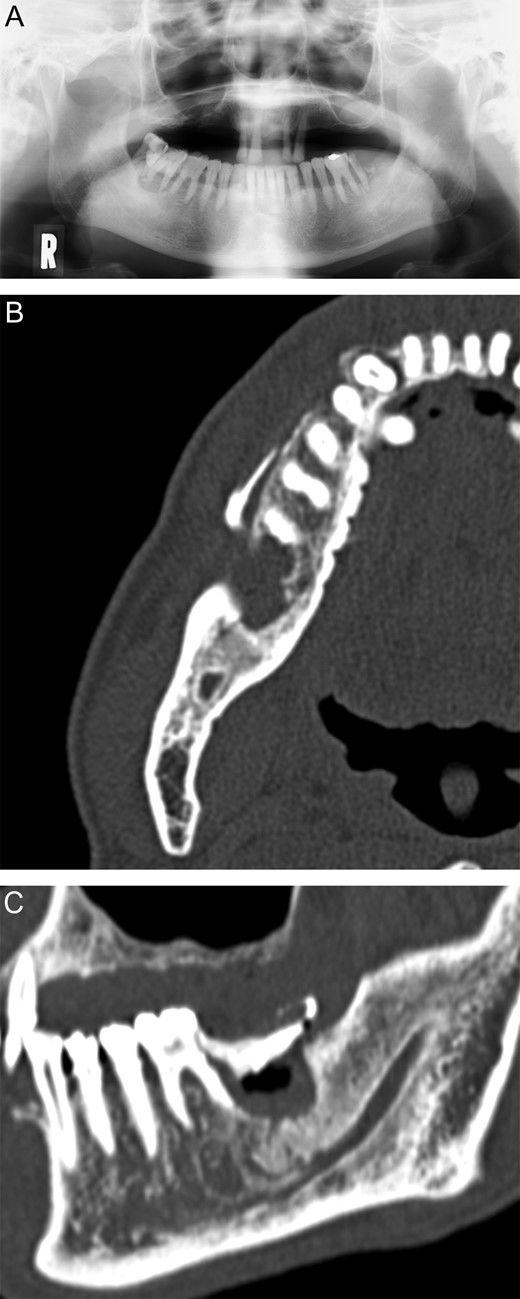

(A) Panoramic radiograph on 12 June 2012. (B) Coronal view of the computed tomography images on 25 June 2012. (C) Sagittal view of the computed tomography images on 25 June 2012.

The Internal Medicine Department assigned a clinical diagnosis of CMMoL, based on the blood and bone marrow examinations conducted on 13 June 2012. Computed tomography on June 25 indicated that bone absorption had nearly reached the right inferior alveolar canal, and a ring of sequestrum was present under tooth 47 (Fig. 2B and C). We diagnosed right mandibular osteomyelitis, based on these clinical features.